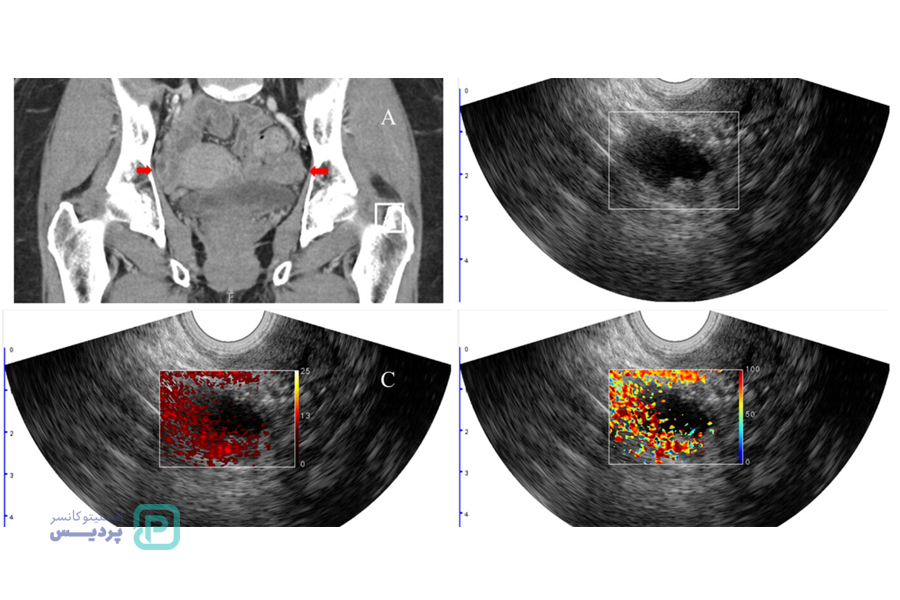

تشخیص سرطان تخمدان با سونوگرافی

تشخیص سرطان تخمدان با سونوگرافی لگنی یکی از روشهای رایج و مؤثر است که به پزشک کمک میکند ساختار و وضعیت تخمدانها را بررسی کند. در این روش، با استفاده از امواج صوتی تصاویر دقیقی از تخمدانها و بافتهای اطراف آن ایجاد میشود. سونوگرافی ترانسواژینال نیز نوعی از سونوگرافی است که در آن دستگاهی بهطور مستقیم به داخل واژن وارد میشود و تصاویری با جزئیات بیشتر از تخمدانها و رحم به دست میآید.

سونوگرافی به پزشک امکان میدهد تا وجود هرگونه توده یا کیست غیرطبیعی را در تخمدانها شناسایی کند و اندازه، شکل و خصوصیات آن را بررسی نماید. اگرچه سونوگرافی میتواند تغییرات مشکوک را نشان دهد، اما برای تأیید قطعی سرطان، ممکن است آزمایشهای بیشتری مانند آزمایش خون CA-125، سیتیاسکن، یا نمونهبرداری از بافت نیز لازم باشد.